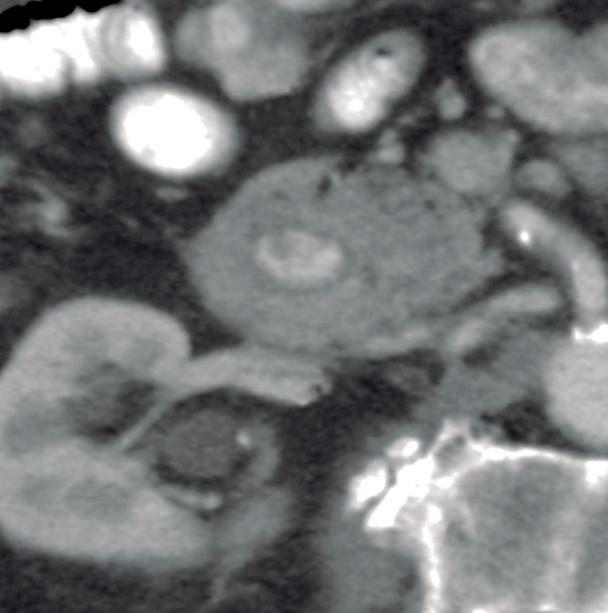

Páncreas Circumportal

El páncreas engloba a la vena mesentérica superior o vena porta, en lugar de rodear al duodeno como sucede en el páncreas anular (Figura 14). Tiene una prevalencia de hasta 2,5% según algunas series, por ende, no es tan infrecuente encontrarlo en estudios por imágenes. Se

A B

postula que su origen está relacionado con una anomalía en la rotación y fusión del brote ventral con el dorsal. Es una condición asintomática, pero cobra relevancia reconocerla e informarla en pacientes que serán sometidos a cirugía del páncreas, con el fin de reducir complicaciones, particularmente la fístula pancreática.25, 26

A) Resonancia magnética, secuencia T1 sin contraste, plano axial. Tejido pancreático con típica señal hiperintensa en secuencia de ponderación tisular T1 (cabezas de flecha), rodeando a la vena porta (VP). B) Resonancia magnética, secuencia T1 con contraste, fase portal, plano axial. VP: vena porta, VE: vena esplénica, AMS: arteria mesentérica superior.

Figura 14. Páncreas circumportal